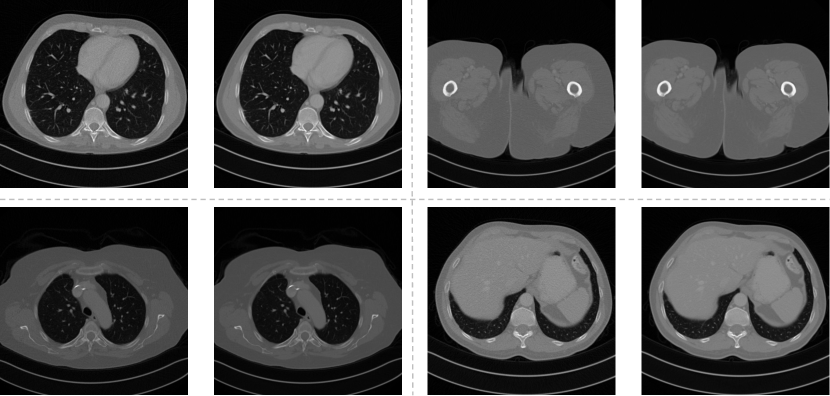

The dataset publicly released as part of the 2016 NIH-AAPM-Mayo Clinic LDCT Grand Challenge [27] has been employed for both training and testing of the model. This dataset comprises pairs of images captured at full dose (acquired at 120 and 200 quality reference , or ) and quarter dose (simulated data acquired at 120 and 50 ). It includes abdominal CT scans from ten anonymized patients. For evaluation purposes, data from patient were utilized, while the remaining nine patients’ datasets were used for model training.

CT scans were originally in DICOM (Digital Imaging and Communications in Medicine) format, with pixel dimensions of . To expedite processing, we used the Python library pydicom to convert the raw data into NumPy arrays, which were then preprocessed and normalized. Data augmentation techniques were also applied. We generated additional training images by randomly rotating (90, 180, or 270 degrees) and flipping (vertically and horizontally) the original images to further enhance the network’s performance. Figure 4 showcases a subset of sample pairs from the dataset.